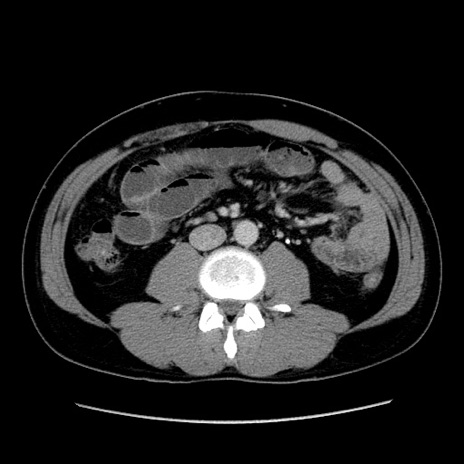

症例4(横断像)

【症例】30歳代男性

【主訴】腹痛、嘔吐

【現病歴】昨晩から突然の腹痛あり、その後嘔吐、軟便も出現。腹痛が改善しないため救急搬送となる。2日前にしめ鯖の食事歴あり。

【身体所見】意識清明、苦悶様、BP 135/90mmHg、BT 35.7℃、腹部:平坦、やや硬、心窩部〜臍部に自発痛、圧痛あり、筋性防御+、反跳痛-

【データ】WBC 8100、CRP 0.57